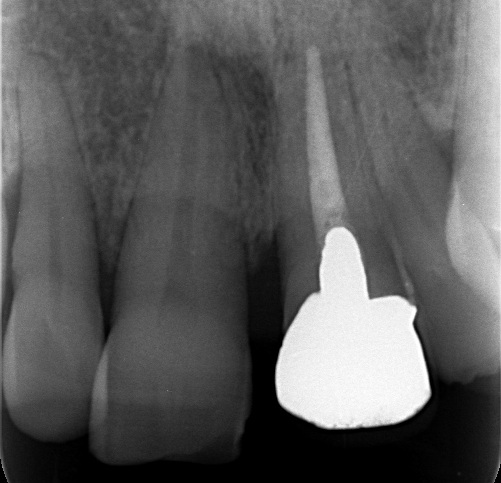

“実際の実施例1”

この患者様は、口腔内全体において重度の歯周病が生じており、歯磨き指導、クリーニング、Flap手術等を行ったが、歯周ポケットが深すぎるため

ブルーラジカル適用症例と診断し、施術を行いました。

(実施前)

施術前のレントゲンと口腔内写真です。施術前にプラークの除去を行ってから、施術します。